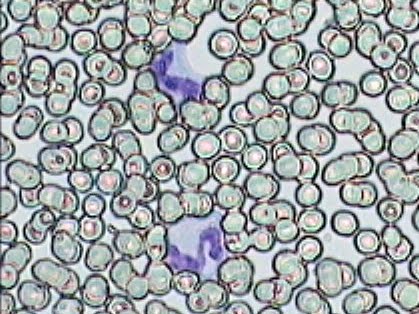

Imágenes tomadas de las preparaciones de los alumnos de 3º ESO sobre un frotis sanguíneo